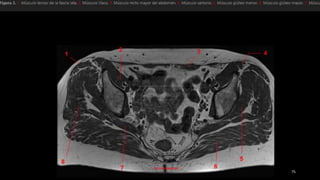

• tensor de la fascia lata (tfi), el psoasilíaco

(Ips), el sartorio (sa) y el recto femoral (rf).

• los vientres musculares se representan en

gris y los tendones, en negro.

• Punta de flecha blanca señala el tendón del

recto femoral.

• flecha, fascia lata.

• músculos pectíneo

(Pt), aductor largo (1),

aductor corto (2),

aductor mayor (3) y

recto interno (Gr).

• ObtE, obturador

externo

• tensor dela fascia lata (tfi), el psoasilíaco (Ips), el sartorio (sa) y el recto femoral (rf). • los vientres musculares se representan en gris y los tendones, en negro. • Punta de flecha blanca señala el tendón del recto femoral. • flecha, fascia lata.

• músculos pectíneo (Pt),aductor largo (1), aductor corto (2), aductor mayor (3) y recto interno (Gr). • ObtE, obturador externo

• el tensorde la fascia lata (Tfn y el sartorio (Sa) se originan en la espina ilíaca anterosuperior (flecha recta). • recto femoral (Rf se origina en la espina ilíaca anteroinferior (punta de flecha) , • músculos ilíaco y psoasilíaco convergen en un tendón común en un punto distal que se inserta en el trocánter menor (flecha curva). • músculo pectíneo (Pe) • rama superior del pubis (Pb).